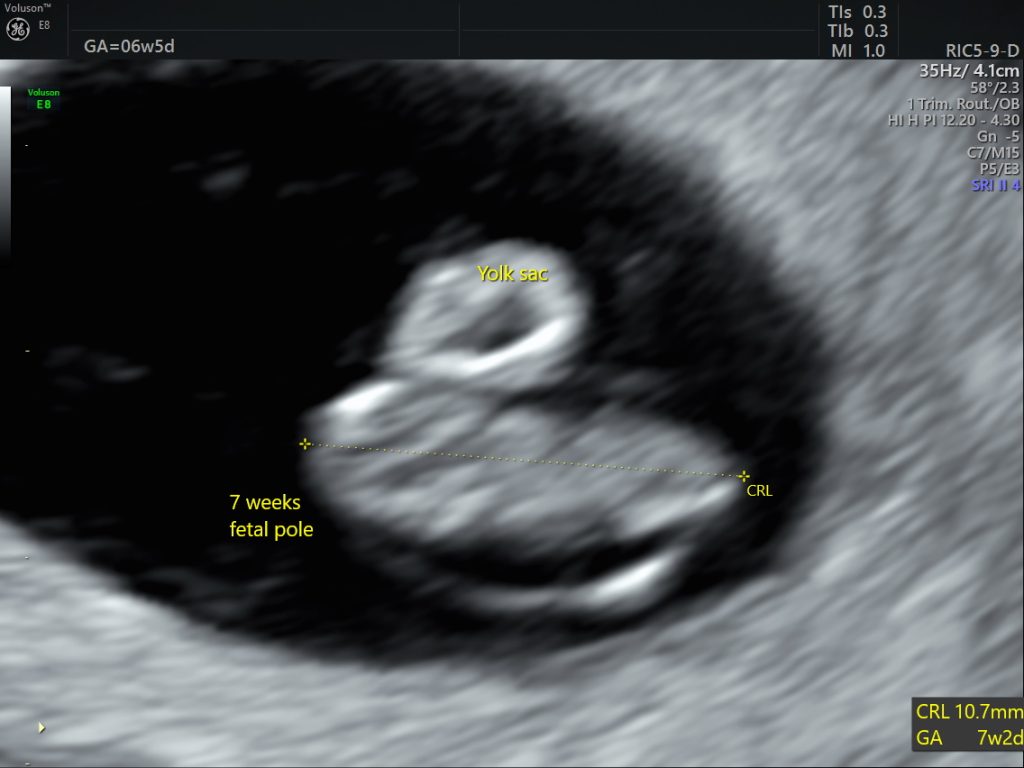

Age:

We can estimate the age of the baby (fetal pole) from 6 wks and it can be accurate within a couple of days early on.

ANATOMY: We can see the yolk sac as early as 5 weeks, this is even before the baby is seen. This can also confirm the correct position of the baby but we will not see the baby at 5 weeks, thats why we recommended to come after 6 wks. Although, we will never say no if you want to check position. We also check the ovaries and the surrounding area to make sure there is no pathology.